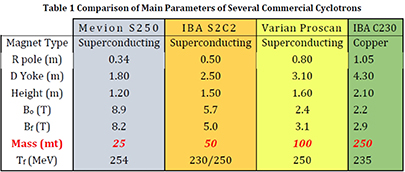

Figure 5.9. Comparison of main parameters of several commercial cyclotrons; see 'Compact, low-cost, lightweight, superconducting, ironless cyclotrons for hadron radiotherapy', PSFC/RR-19-5.

Most proton therapy facilities use cyclotrons to produce the beam, as these accelerators are compact, have only a few tuning parameters, and are thus simple to operate. Over the last three decades the size and weight have dramatically shrunk by factors 3–10 while the magnetic fields using superconductivity were increased up to a factor 4 (figure 5.9). These improvements still show the potential of cyclotrons while parallel developments like proton linacs are still larger and have a much more complex technique. But the actual cyclotron generation consists still of fixed energy machines, which demands a degrader for energy variation causing two main drawbacks: (a) high local beam losses and (b) relatively low currents for mid-depth and skin-deep tumours, which may be a problem to use the FLASH-based treatment procedure. To overcome these disadvantages first studies of energy-variable cyclotrons were undertaken and published. These show the possibilities to consequently advance the cyclotron systems to lighter, high-field superconducting arrangements, but now iron-free and thus capable to vary the magnetic field and energy in reasonable times. In addition, the produced currents of such a setting do not depend on the energy because no loss mechanism is involved anymore. The resulting machines would be 'FLASH'-ready and have the additional possibility to be enhanced to 3He/4He beam combined with proton therapy in one cyclotron setup. More simulation studies and prototype constructions are needed to reach these goals in the next 5–10 years.

Energy-variable cyclotrons